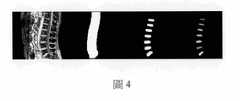

圖4從左至右依次是:整個腰部的側面核磁共振圖像;與之靠近的中間長條狀的為脊椎的掩模區、單個椎間盤的掩模區、最後是單個椎間盤的分割圖像的示意圖。Figure 4 from left to right is: side MRI images of the entire waist; the middle strip adjacent to it is the mask area of the spine, the mask area of a single intervertebral disc, and finally the segmented image of a single intervertebral disc Schematic.